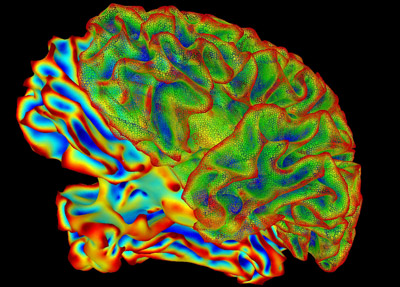

“When neural circuits all work, it’s like a symphony,” says Dr. Allen Burton, medical director of neuromodulation at Abbott. “But sometimes, somebody inherits a bad gene, or gets injured, or something nobody knows goes amiss.” As a result of this unknown cause, certain neural circuits might start firing over and over again. Our brains think this repeated signal indicates a continuing problem. “All of a sudden, instead of having normal sensation, you have pain, or a terrible ongoing sensation that won’t go away,” Burton says.

“In the last two years, neuroscience has made more progress than in all of recorded history toward understanding neural circuitry, how thoughts are processed, and different brain-disease states,” says Burton. “This burst stimulator fits into that progress: We’re right on the cusp of taking the knowledge that these scientists are getting and translating it into treatments that help people.”